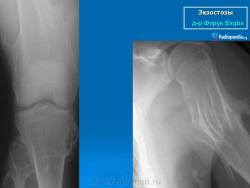

Локализация остеохондромы: частота поражения отдельных костей различна; нижний коней бедренной кости, верхние отделы плечевой и большеберцовой костей поражаются более чем у половины больных. На всем протяжении остеохондрома покрыта надкостницей. Она может быть обнаружена и в других костях, за исключением костей лицевого черепа. Все же поражение костей позвоночника, кистей рук и стоп встречается редко. При рентгенологическом исследовании видна типичная картина узкого или широкого выроста вблизи эпифизарной части пораженной кости. Обычно плотность узла неоднородная, имеются многочисленные плотные участки, соответствующие обызвествленным хрящевым долькам. Хрящевая «шапочка» большей частью не определяется, поскольку хрящ остается необызвествленным. Она может быть выявлена только при магнитно-резонансной томографии.

Костно-хрящевые экзостозы